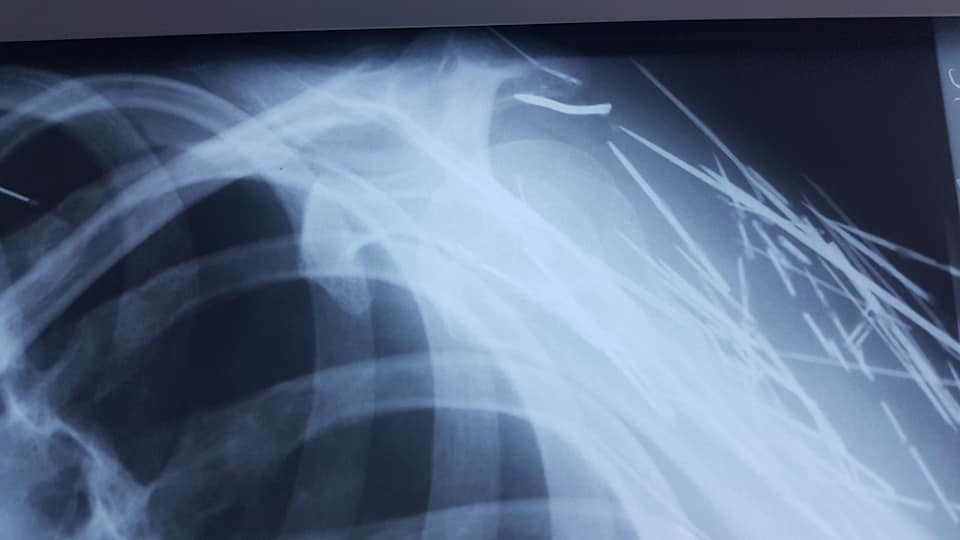

Un bărbat din județul Botoșani a ajuns la spital cu mai multe ace înfipte în tot corpul. El a ajuns pe mâna unui medic de la Secția din Săveni a Spitalului Județean Botoșani, care a rămas uimit când a văzut ce se află în corpul bărbatului.

„Ce se mai poate găsi în corpul unui pacient. Ace, cuie, sarme. In 40 de ani de când mă învârt în ale medicinii nu am mai vazut asa ceva. Ca o precizare este vorba de un pacient cu tulburări afective si psihice. Acele sunt de mult acolo, umăr, gât, axila. Corpul le acceptă. Ce sa facă, săracul. Este o victimă”, a spus medicul Elena Cardaș.